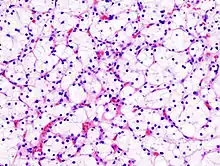

Histopathology

The gross and microscopic appearance of renal cell carcinomas is highly variable. The renal cell carcinoma may present reddened areas where blood vessels have bled, and cysts containing watery fluids.[58] The body of the tumour shows large blood vessels that have walls composed of cancerous cells. Gross examination often shows a yellowish, multilobulated tumor in the renal cortex, which frequently contains zones of necrosis, haemorrhage and scarring. In a microscopic context, there are four major histologic subtypes of renal cell cancer: clear cell (conventional RCC, 75%), papillary (15%), chromophobic (5%), and collecting duct (2%). Sarcomatoid changes (morphology and patterns of IHC that mimic sarcoma, spindle cells) can be observed within any RCC subtype and are associated with more aggressive clinical course and worse prognosis. Under light microscopy, these tumour cells can exhibit papillae, tubules or nests, and are quite large, atypical, and polygonal.

Recent studies have brought attention to the close association of the type of cancerous cells to the aggressiveness of the condition. Some studies suggest that these cancerous cells accumulate glycogen and lipids, their cytoplasm appear "clear", the nuclei remain in the middle of the cells, and the cellular membrane is evident.[59] Some cells may be smaller, with eosinophilic cytoplasm, resembling normal tubular cells. The stroma is reduced, but well vascularised. The tumour compresses the surrounding parenchyma, producing a pseudocapsule.[60]

The most common cell type exhibited by renal cell carcinoma is the clear cell, which is named by the dissolving of the cells' high lipid content in the cytoplasm. The clear cells are thought to be the least likely to spread and usually respond more favourably to treatment. However, most of the tumours contain a mixture of cells. The most aggressive stage of renal cancer is believed to be the one in which the tumour is mixed, containing both clear and granular cells.[61]